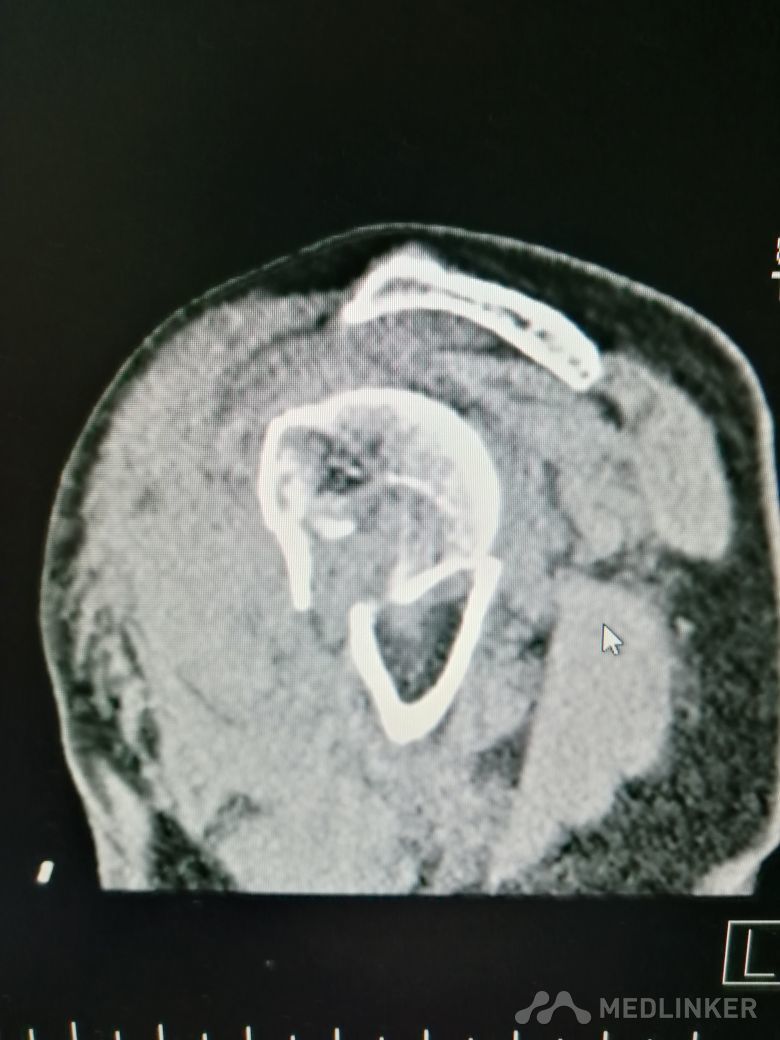

肱骨近端骨折 Neer IV型

患者,女性,55岁,因外伤致左肩疼痛六小时入院,既往无其他慢性病史

查体 右肩肿胀,畸形,活动受限,压痛,皮下淤血,右桡动脉搏动存在

完善相关检查,在腰麻下行右肱骨近端骨折切开复位内固定术

肱骨近端骨折占到肱骨骨折的45%,肱骨近端锁定钢板具有低切迹、高弹性、生物力学性能优良等特点,可以起到角度稳定控制旋转的作用。但是对于严重粉碎性肱骨近端骨折而言,单纯的肱骨近端锁定钢板不一定能够提供稳定的固定,手术之后仍有可能出现内翻塌陷、前后成角、螺钉切出、骨折畸形愈合、骨折不愈合等并发症。